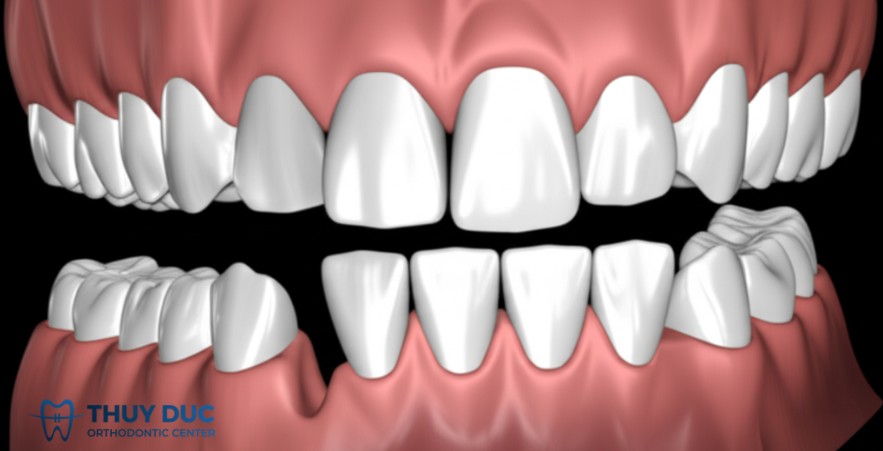

Bệnh nhân có các dạng sai khớp cắn như cắn sâu, cắn chéo, cắn ngược hoặc cắn hở. Những tình trạng này không chỉ ảnh hưởng chức năng ăn nhai mà còn khiến việc phục hình trở nên không bền vững và thiếu hiệu quả.

Một người có khớp cắn sâu, các răng cửa hàm trên che phủ hoàn toàn răng cửa hàm dưới. Nếu bọc sứ thẩm mỹ mà không chỉnh nha trước, răng sứ dễ bị vỡ do lực cắn trực tiếp. Cần chỉnh nha để đưa khớp cắn về đúng tương quan, sau đó mới bọc sứ.

Bệnh nhân muốn cải thiện thẩm mỹ vùng răng cửa bằng bọc sứ, nhưng răng hiện tại lệch nhẹ, chen chúc hoặc chìa ra một chút.

Một bệnh nhân nữ có răng cửa chìa nhẹ và không đều nhau. Nếu bọc sứ trực tiếp sẽ phải mài sâu và vẫn không đạt tỉ lệ lý tưởng. Chỉnh nha nhẹ trong vài tháng giúp đều răng, sau đó bọc sứ sẽ đẹp tự nhiên hơn, bền hơn và bảo tồn tối đa răng thật.